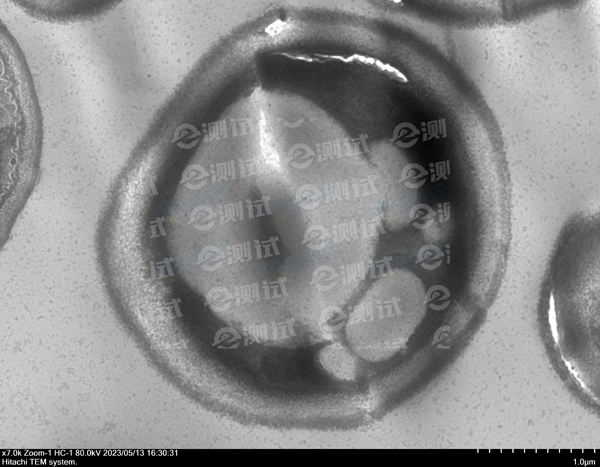

白色念珠球菌做TEM項(xiàng)目,拍到的照片中顯示菌體中央有一折線,這是什么原因造成的?

真菌細(xì)胞壁較厚,滲透難度大。

改善方法:固定液更換,具體配方:4%多聚甲醛+5%戊二醛: 溶解2g多聚甲醛于25 ml雙蒸水中,80°C水浴,搖動使之溶化后加1-3滴1M NaOH,使溶液澄清。冷卻后加10 ml25%戊二醛,再加15 ml 0.2PB,調(diào)pH備用,再加入Triton X-100(終濃度3% )。 此固定液中含多聚甲醛4%,戊二醛5%,屬高滲液,但固定效果不錯,尤其對細(xì)胞內(nèi)的微管保存較好。